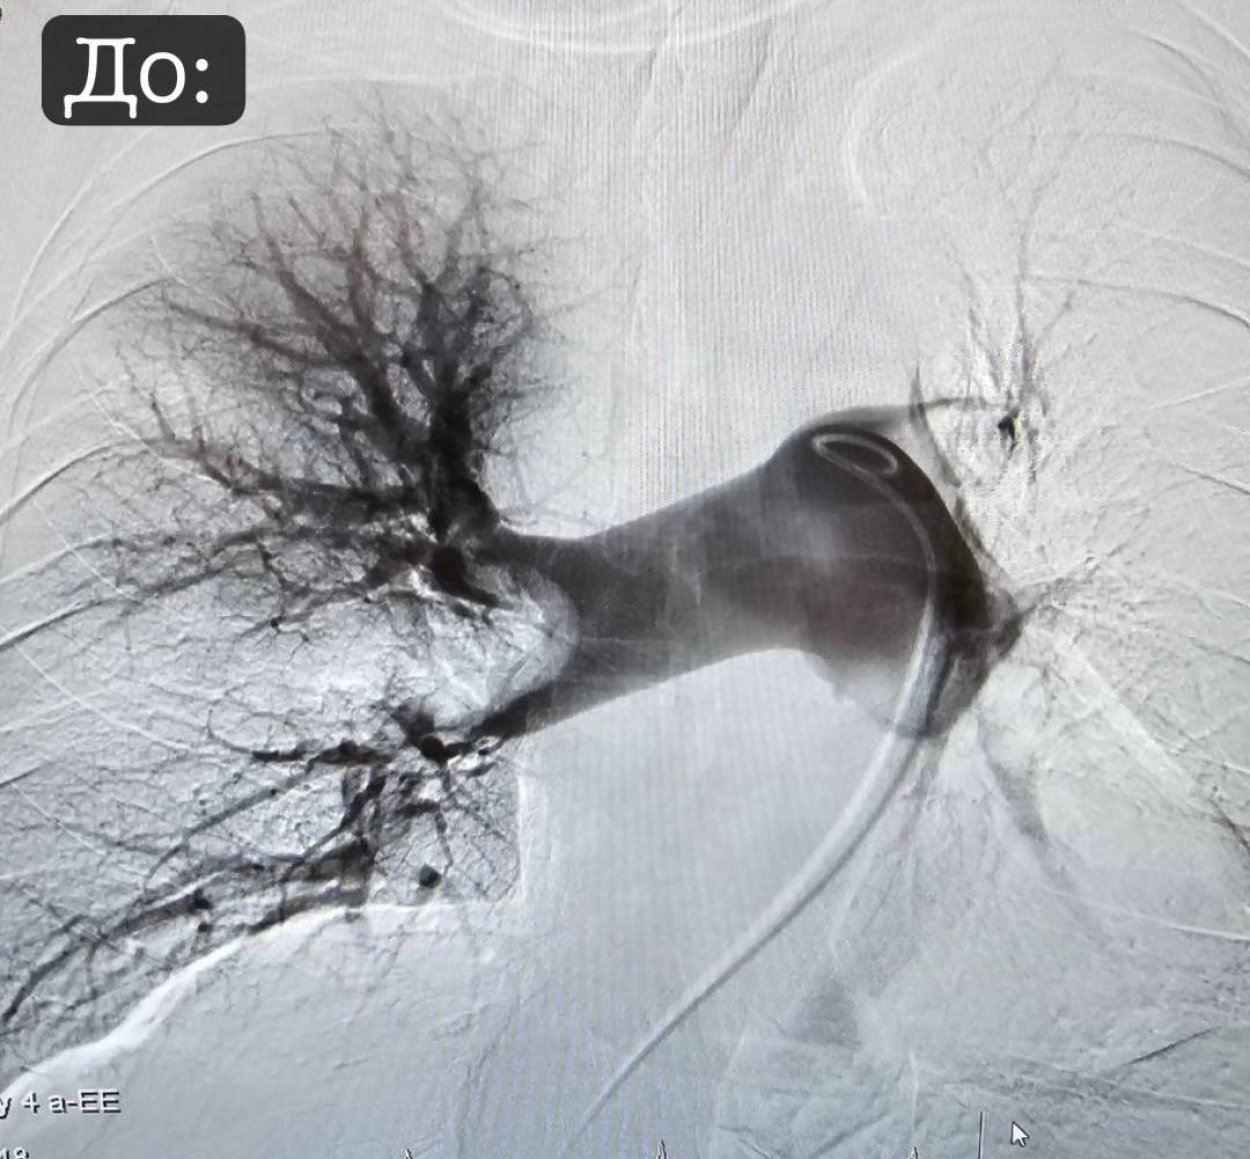

В орской больнице появился уникальный аппарат. Он позволяет доставлять лекарство прямо к тромбу с помощью тонкой трубочки (катетера) и ультразвука. Как это работает:

- катетер вводится прямо в место образования тромба

- специальный ультразвуковой датчик на конце катетера помогает разрушить тромб и равномерно распределить лекарство по нему